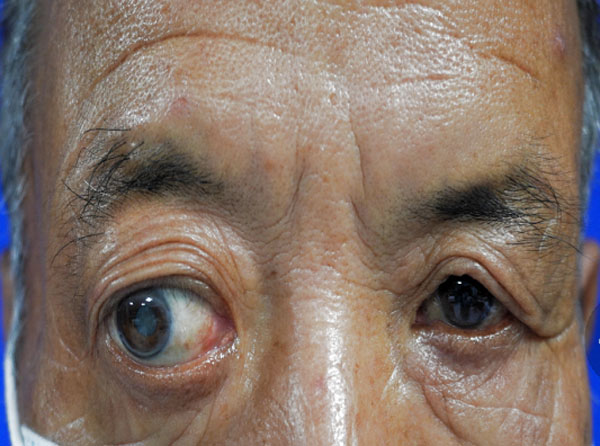

眼眶腫瘤,可能是會讓患者失去光明的“定時炸彈”。

眼球突出是最常見的臨床表現,當然少數患者是眼球本身的疾患引起眼球增大,如高度近視,我們稱為假性眼球突出。眼突較輕時,僅外觀不對稱;程度較重時,眼球會移位、運動障礙、復視、視力下降,直至眼瞼無法閉合,引起暴露性角膜炎。如果是惡性腫瘤造成的,還可能遠處轉移,危及生命。

眼球突出并不一定意味著腫瘤,如外傷性突眼,主要是頭面部外傷引起眶骨骨折、眶內出血所致;內分泌性突眼與甲狀腺功能亢進有關,還會伴有上瞼退縮的特征性表現;炎癥性突眼有急性的蜂窩組織炎和慢性炎癥,常伴紅、腫、熱、痛等表現;血管性突眼的特點是低頭、屏氣時眼突會加重,因此呈間歇性。

當您因眼球突出而就診時,醫生會詢問一些相關“線索”,如年齡、病變發展速度、有無外傷、有無疼痛甚至全身血液情況、甲狀腺功能等等,都對正確的鑒別診斷極為重要。例如小兒眼球突出,特別是雙側者,就需排除白血病。

B超、CT、核磁共振等影像學檢查都必不可少,可以提供病變的位置、大小。細針穿刺活檢創傷小,但可以獲取細胞學標本,幫助診斷。有的病例需要手術活檢進行病理檢查明確診斷,指導治療。

就腫瘤而言,手術完整摘除是最常用的治療手段,由于在眼眶有限的空間內,集中了眼球、視神經、眼外肌、供養血管等重要結構,因此手術是有難度的。醫生根據眼眶腫瘤的位置選擇最佳的手術路徑,借助于先進的頭戴放大鏡系統,使手術操作更加準確,最大程度減少了并發癥。